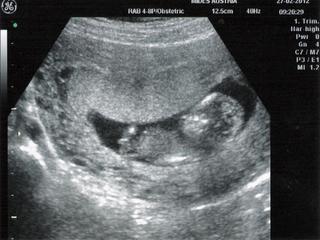

@petraas 🙂 hej, srandovne su... vcera som písala, to naše škvŕňa sa tiez zobudilo a natahovalo nozicky, potom mávalo ručičkami, a ked zavolali aj manzela, tak sa prudko otočilo akoby klaklo na kolienka a zacalo hrabat ručičkami... ako psík 🙂 zacala som sa smiat, tak sa asi urazilo, a otočilo sa chrbtom... takze mame take fotky nic moc... len takého "kostlivca" hlavička a bruško s predu aj zo zadu 🙂 najzretelnejšia je len hlavicka... 🙂